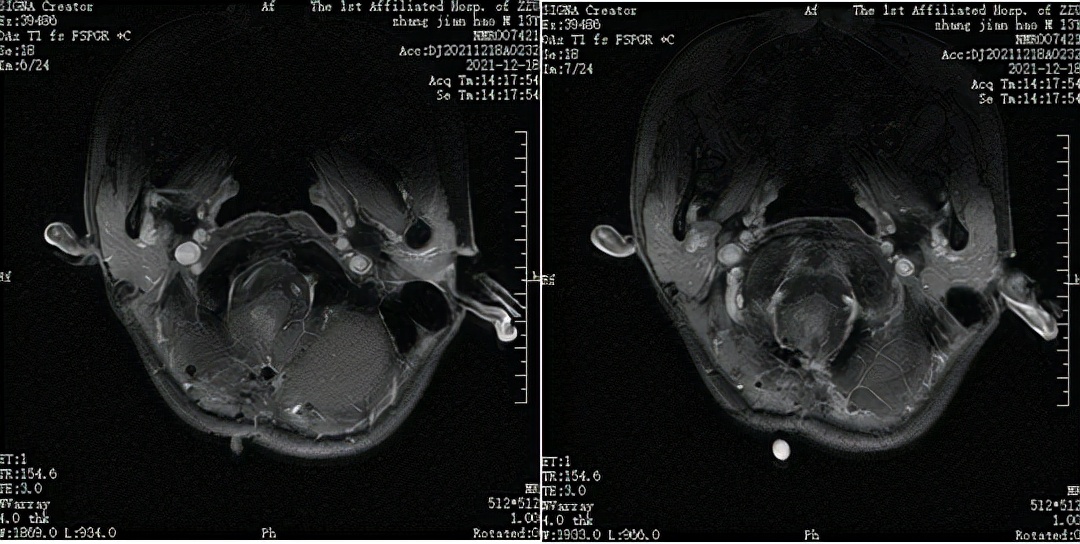

△治疗前(2021-11-17) MRI T1WI+C 横断位

△第一周期声动力治疗后(2021-12-18) MRI T1WI+C 横断位

△第二周期声动力治疗后(2021-03-01) MRI T1WI+C 横断位